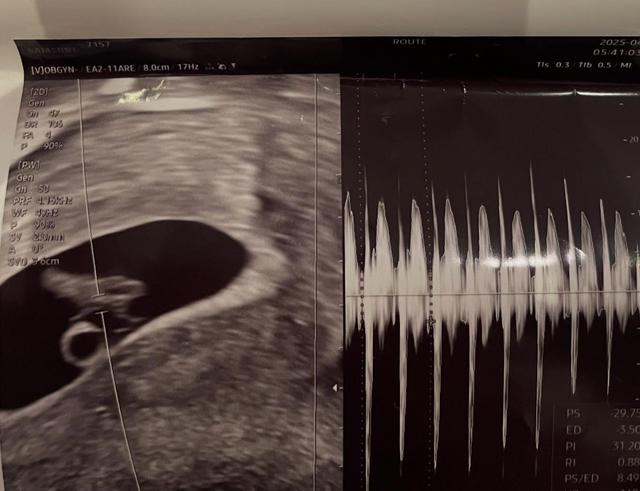

서민재는 5월 4일, 자신의 인스타그램 스토리를 통해 남자친구와의 문자 내용, 초음파 사진, 실명, 학교, 학번, 아버지의 직장 정보 등을 공개했습니다. 그녀에 따르면, 임신 사실을 통보한 후 남자친구는 연락을 피했고, 최근에는 스토킹 혐의로 형사 고소를 예고했다고 밝혔습니다.